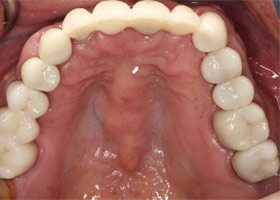

治療後

proimages/case/Artificial_implant/after01.jpg